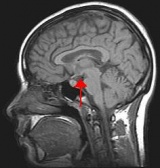

暈動病的發病機制尚未完全明了,主要與影響前庭功能有關。前庭器的內耳膜迷路的橢圓囊和球囊的囊斑是感受上下和左右的直線運動,三個半規管毛細胞感受鏇轉運動。當囊斑或毛細胞受到一定量的不正常運動刺激所引起的神經衝動,依次由前庭神經傳至前庭神經核,再傳至小腦和下丘腦,因而引起一系列以眩暈為主要症狀的臨床表現。前庭受刺激後影響網狀結構,引起血壓下降和嘔吐。前庭神經核通過內側縱束纖維至眼肌運動核引起眼球震顫。小腦和下丘腦受神經衝動後引起全身肌肉張力改變。暈動病與視覺可能有一定關係。例如,當人們凝視快速運動或鏇轉的物體時也同樣可引起本病。小腦受刺激亦可能為本病的又一機理。此外,高溫、高濕、通風不良、噪音、特殊氣味、情緒緊張、睡眠不足、過度疲勞、飢餓或過飽、身體虛弱、內耳疾病等均易誘發本病。